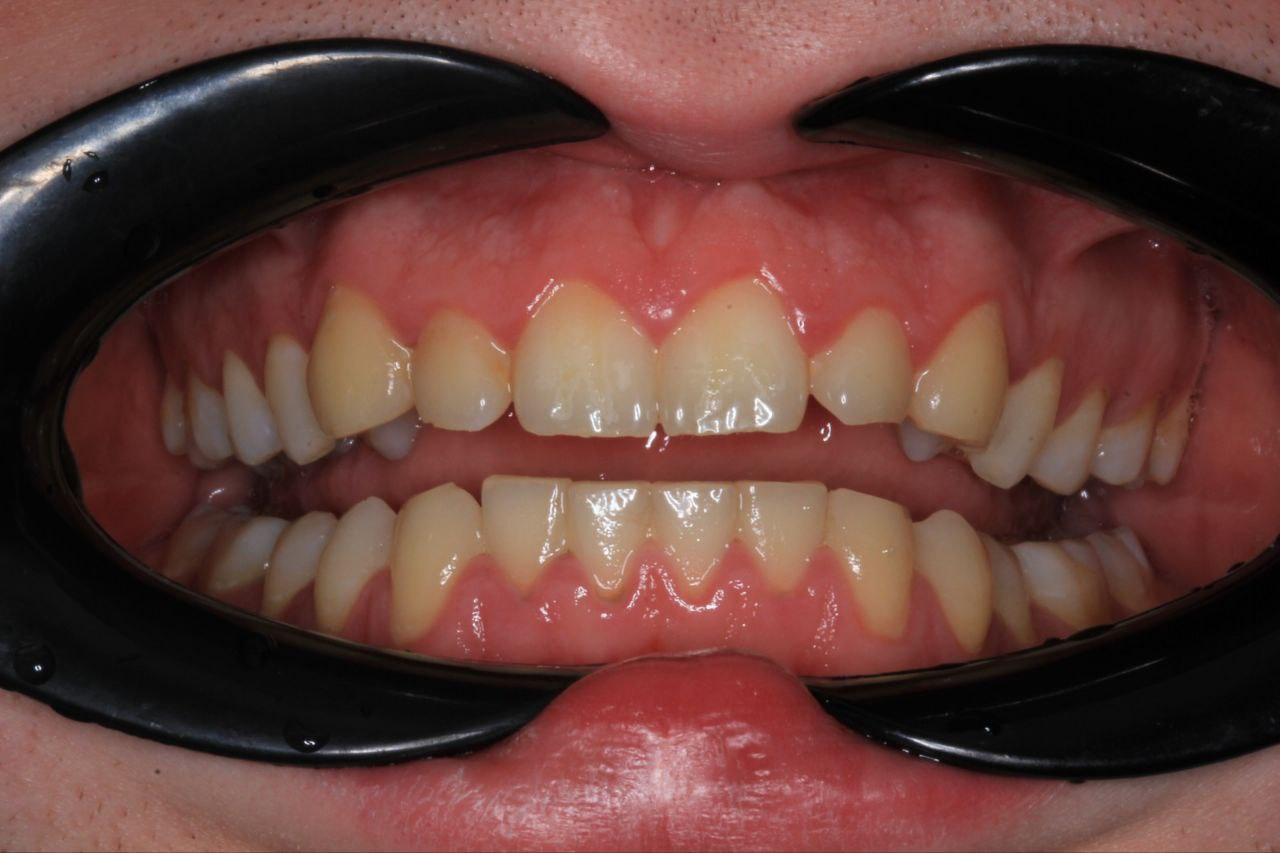

554x750

>>1631979 (OP)

Десны, на месте где зубы в них входят такая вот хуйня, отметил рядом если не понятно. Это начало парадонтита или чего-то такого? Камень года 3 не ходил чистить, каюсь. Есть связь с камнем?